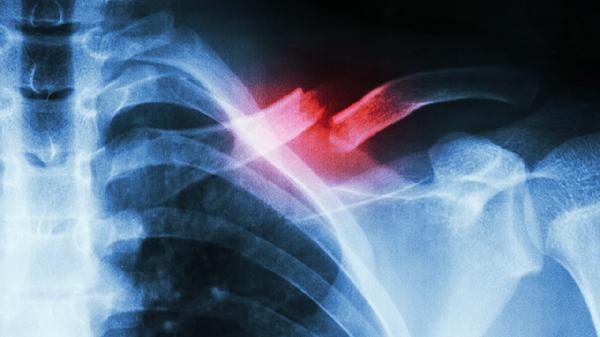

肋骨骨折后一般需要7-14天才能洗澡,具体时间需根据骨折严重程度、愈合情况及医生建议综合判断。

肋骨骨折后洗澡时间主要取决于骨折愈合进程。轻微骨折未伴随其他损伤时,7天后可尝试短时间温水淋浴,但需避免用力搓洗或长时间浸泡。此时骨折端初步纤维连接,疼痛明显减轻,但局部仍存在肿胀,洗澡时应注意保护患处,防止摔倒或碰撞。中度骨折伴随少量胸腔积液或软组织挫伤时,建议10-12天后洗澡,需确保胸带固定牢固,水温控制在38-40摄氏度,时间不超过10分钟。严重多发性骨折合并血气胸等并发症时,须严格遵医嘱,通常需14天以上待胸腔引流管拔除、影像学确认骨痂形成后再考虑洗澡。无论何种情况,洗澡前后均应检查胸带固定松紧度,避免使用过热或过冷的水刺激患处,洗后及时擦干并保持伤口干燥。